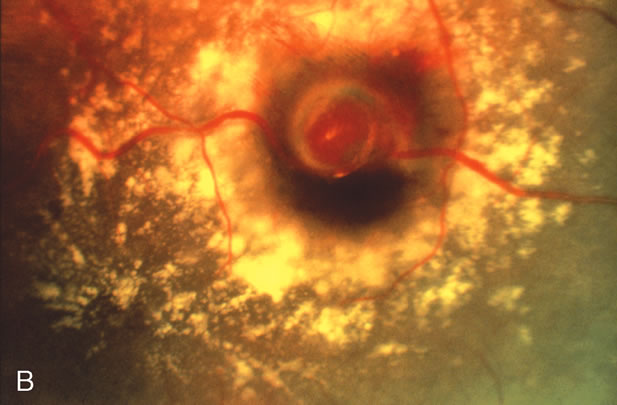

The hallmark for diagnosis of the retinal arterial macroaneurysm is visualization of the macroaneurysm itself (Fig. 1). Because of their relatively large size, macroaneurysms are not usually confused with the microaneurysms of diabetic retinopathy or branch retinal vein occlusion. Microaneurysms typically have a diameter of only 50 to 75 microns and arise from the deeper retinal capillaries; macroaneurysms on the other hand range in size from 100 to more than 500 microns in diameter and arise from the larger retinal arterioles.

Fig. 1. A. Color fundus photograph of a retinal arterial macroaneurysm 750 microns in diameter associated with circinate hard exudates and macular edema involving the fovea. B. High magnification photograph of the same macroaneurysm.